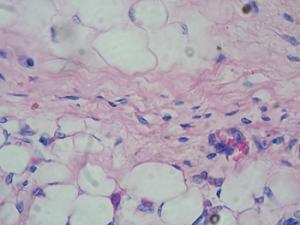

Los diabéticos tienen un mayor riesgo de padecer tuberculosis si son infectados. Al mismo tiempo, esta enfermedad ocasiona un aumento transitorio de azúcar en sangre. Investigadores del <a href="https://www.saludcastillayleon.es/CHLeon/es/complejo-asistencial-universitario-leon" title="Complejo Asistencial Universitario de León" alt="Complejo Asistencial Universitario de León" target="blank">Complejo Asistencial Universitario de León</a> han analizado cómo reaccionan los componentes de la sangre ante la infección y qué diferencias hay entre los individuos más y menos propensos a sufrir tuberculosis.